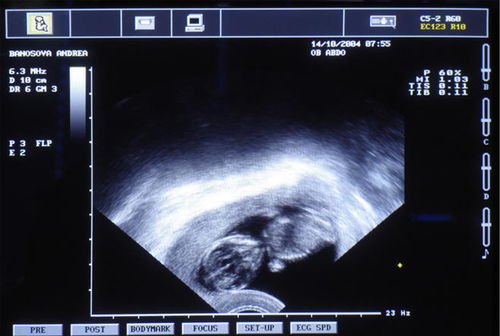

1.什么是陰道b超 通常情況下陰道b超使用的是高頻探頭,相較于其他的婦科b超檢查方式而言功能更加強(qiáng)。而且這種婦科檢查方式可以讓醫(yī)生更加清晰的觀察盆腔器官及細(xì)小病變,除此之外它還可以探測到子宮、卵巢血流情況。

定期做陰道b超對女性健康而言非常重要,因?yàn)樗€可以監(jiān)測卵巢卵泡的發(fā)育情況,對各種可能造成不孕的婦科疾病也可以盡早發(fā)現(xiàn)愛你。 比如像早期異位妊娠、早期子宮內(nèi)膜病變、子宮卵巢腫瘤病變、盆腔膿腫、炎性腫塊等,這些病癥都可以在陰道b超檢查下無處遁形。

所以最好隨身攜帶水瓶及時(shí)補(bǔ)充。 (二)陰道B超:此種檢查方法是在標(biāo)準(zhǔn)的經(jīng)腹超聲機(jī)上再設(shè)置一個(gè)合適的探頭,探頭須套上薄膜,可由檢查者或病人自己將探頭伸入陰道來進(jìn)行檢查,探查盆腔內(nèi)情況。

這種方法不需要憋尿,且由于接近子宮和卵巢,圖像清晰分辨率高,因此,檢查結(jié)果較準(zhǔn)確。 陰道B超注意事項(xiàng): 1、此種方法不適宜有出血者,如月經(jīng)期、陰道不規(guī)則出血;亦不適宜有傳染病者,如陰道炎、性病其他的宮頸疾病、陰道疾病及一些外陰疾病者,以防止感染、交叉?zhèn)魅竞鸵鸪鲅炔涣己蠊?/p>